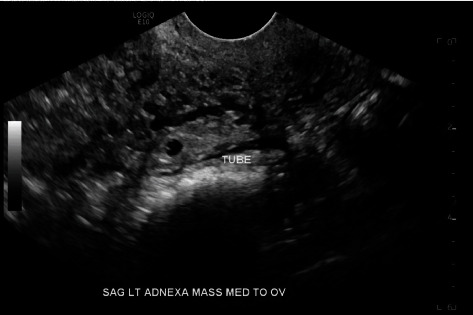

单侧输卵管双胎妊娠的发病率为1/20,000-1/250,000,约有100例报道。在接受药物治疗的六例病例中,有四例取得了成功。一名 24 岁女性因阴道出血和腹部绞痛到急诊科就诊。她的血流动力学稳定,没有急腹症迹象。实验室评估显示她怀孕了,血清中的β-人绒毛膜促性腺激素(b-hCG)为798 mIU/mL。经阴道超声检查(TVUS)发现左侧单侧输卵管妊娠,并伴有卵黄囊。患者选择了以体表面积(BSA)为基础的肌肉注射(IM)甲氨蝶呤(MTX)药物治疗。第4天,患者返回急诊室;她的b-hCG为727 mIU/mL。TVUS 显示双胎左侧输卵管妊娠,卵黄囊和胎儿极无心活动。患者选择继续接受药物治疗,并服用了第二剂基于 BSA 的 IM MTX。第 6 天,患者因腹痛和直肠痛返回急诊室。她的血流动力学稳定,没有急腹症迹象。她的 b-hCG 为 533 mIU/mL。TVUS 显示左侧输卵管持续性双胎妊娠,其中一胎孕龄 5 周,另一胎孕龄 6 周,无破裂迹象。患者继续接受连续的 b-hCG 检查。在首次服用 MTX 31 天后,她的 b-hCG 为

The incidence of unilateral tubal twin pregnancy is 1/20,000-1/250,000 with about 100 reported cases. Four of the six cases that were medically managed were successful. A 24-year-old female presented to the emergency department (ED) with vaginal bleeding and abdominal cramping. She was hemodynamically stable without signs of an acute abdomen. Laboratory evaluation revealed she was pregnant with a serum beta-human chorionic gonadotropin (b-hCG) of 798 mIU/mL. Transvaginal ultrasound (TVUS) revealed a single left tubal pregnancy with a yolk sac. The patient elected medical management with body surface area (BSA)-based intramuscular (IM) methotrexate (MTX). On Day 4, the patient returned to the ED; her b-hCG was 727 mIU/mL. TVUS revealed twin left tubal pregnancies with yolk sacs and fetal poles without cardiac activity. The patient elected to continue medical management with a second dose of BSA-based IM MTX. On Day 6, the patient returned to the ED with abdominal and rectal pain. She was hemodynamically stable without signs of an acute abdomen. Her b-hCG was 533 mIU/mL. TVUS showed persistent twin left tubal pregnancies-one at 5 weeks gestational age and the other at 6 weeks gestational age-without evidence of rupture. The patient continued serial b-hCGs. Thirty-one days after the first dose of MTX, her b-hCG was < 1 mIU/mL. TVUS showed resolution of tubal pregnancies. The patient consented to the publication of this case report. This case documents the successful treatment of spontaneous, unilateral tubal twin pregnancies with two-step dosing of IM MTX.